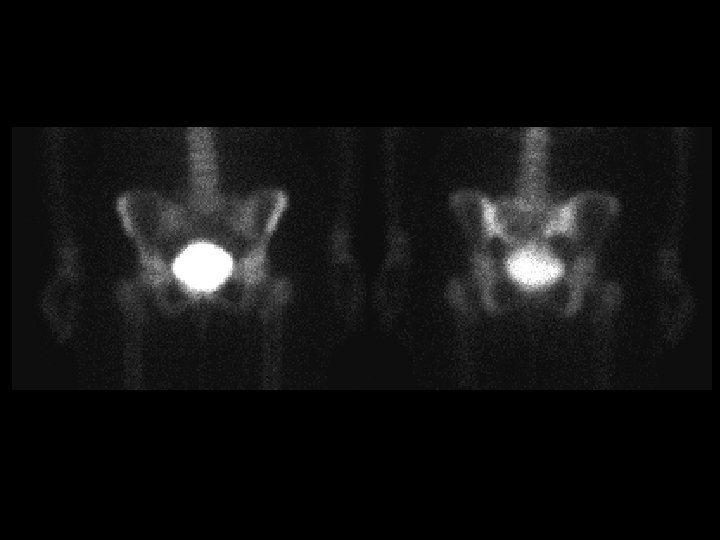

Neuroblastoma • Findings: – Bone scan shows increased uptake in the mid abdomen of a child – MR scan shows a corresponding soft tissue mass with scattered T 1 low sign foci = Ca 2+ • ddx: – NONE! – This is an Aunt Minnie!